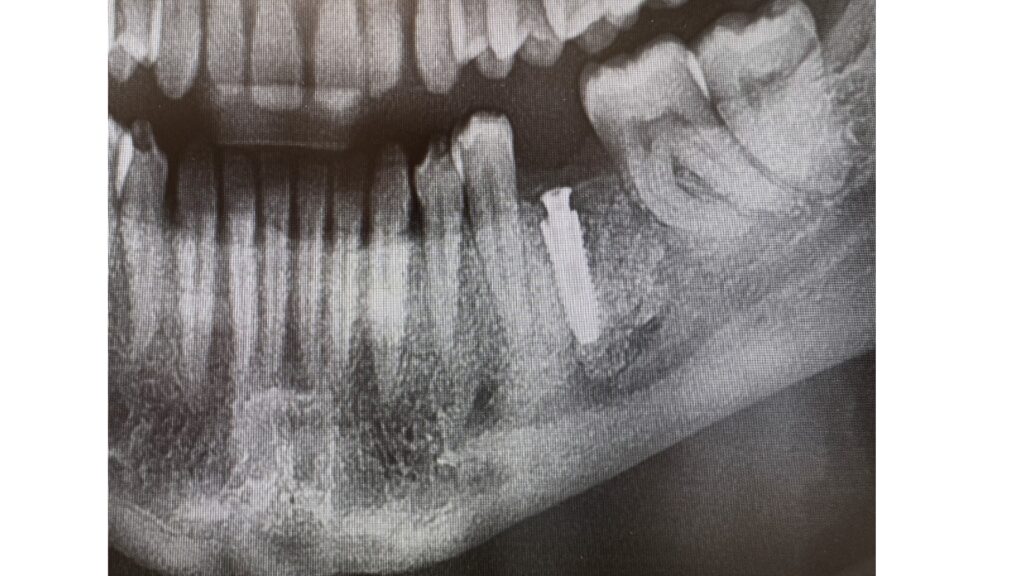

Implantes

Tratamento dentário indicado para substituir dentes perdidos, devolvendo função, conforto e estética ao sorriso de forma duradoura.